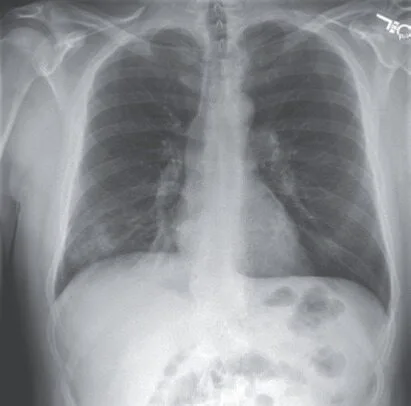

胸片提示右下肺浸润(图1A)。初步考虑为社区获得性肺炎,给予静脉左氧氟沙星治疗(750mg每天一次)。

图1A. 患者住院第1天胸片示右下肺浸润影。